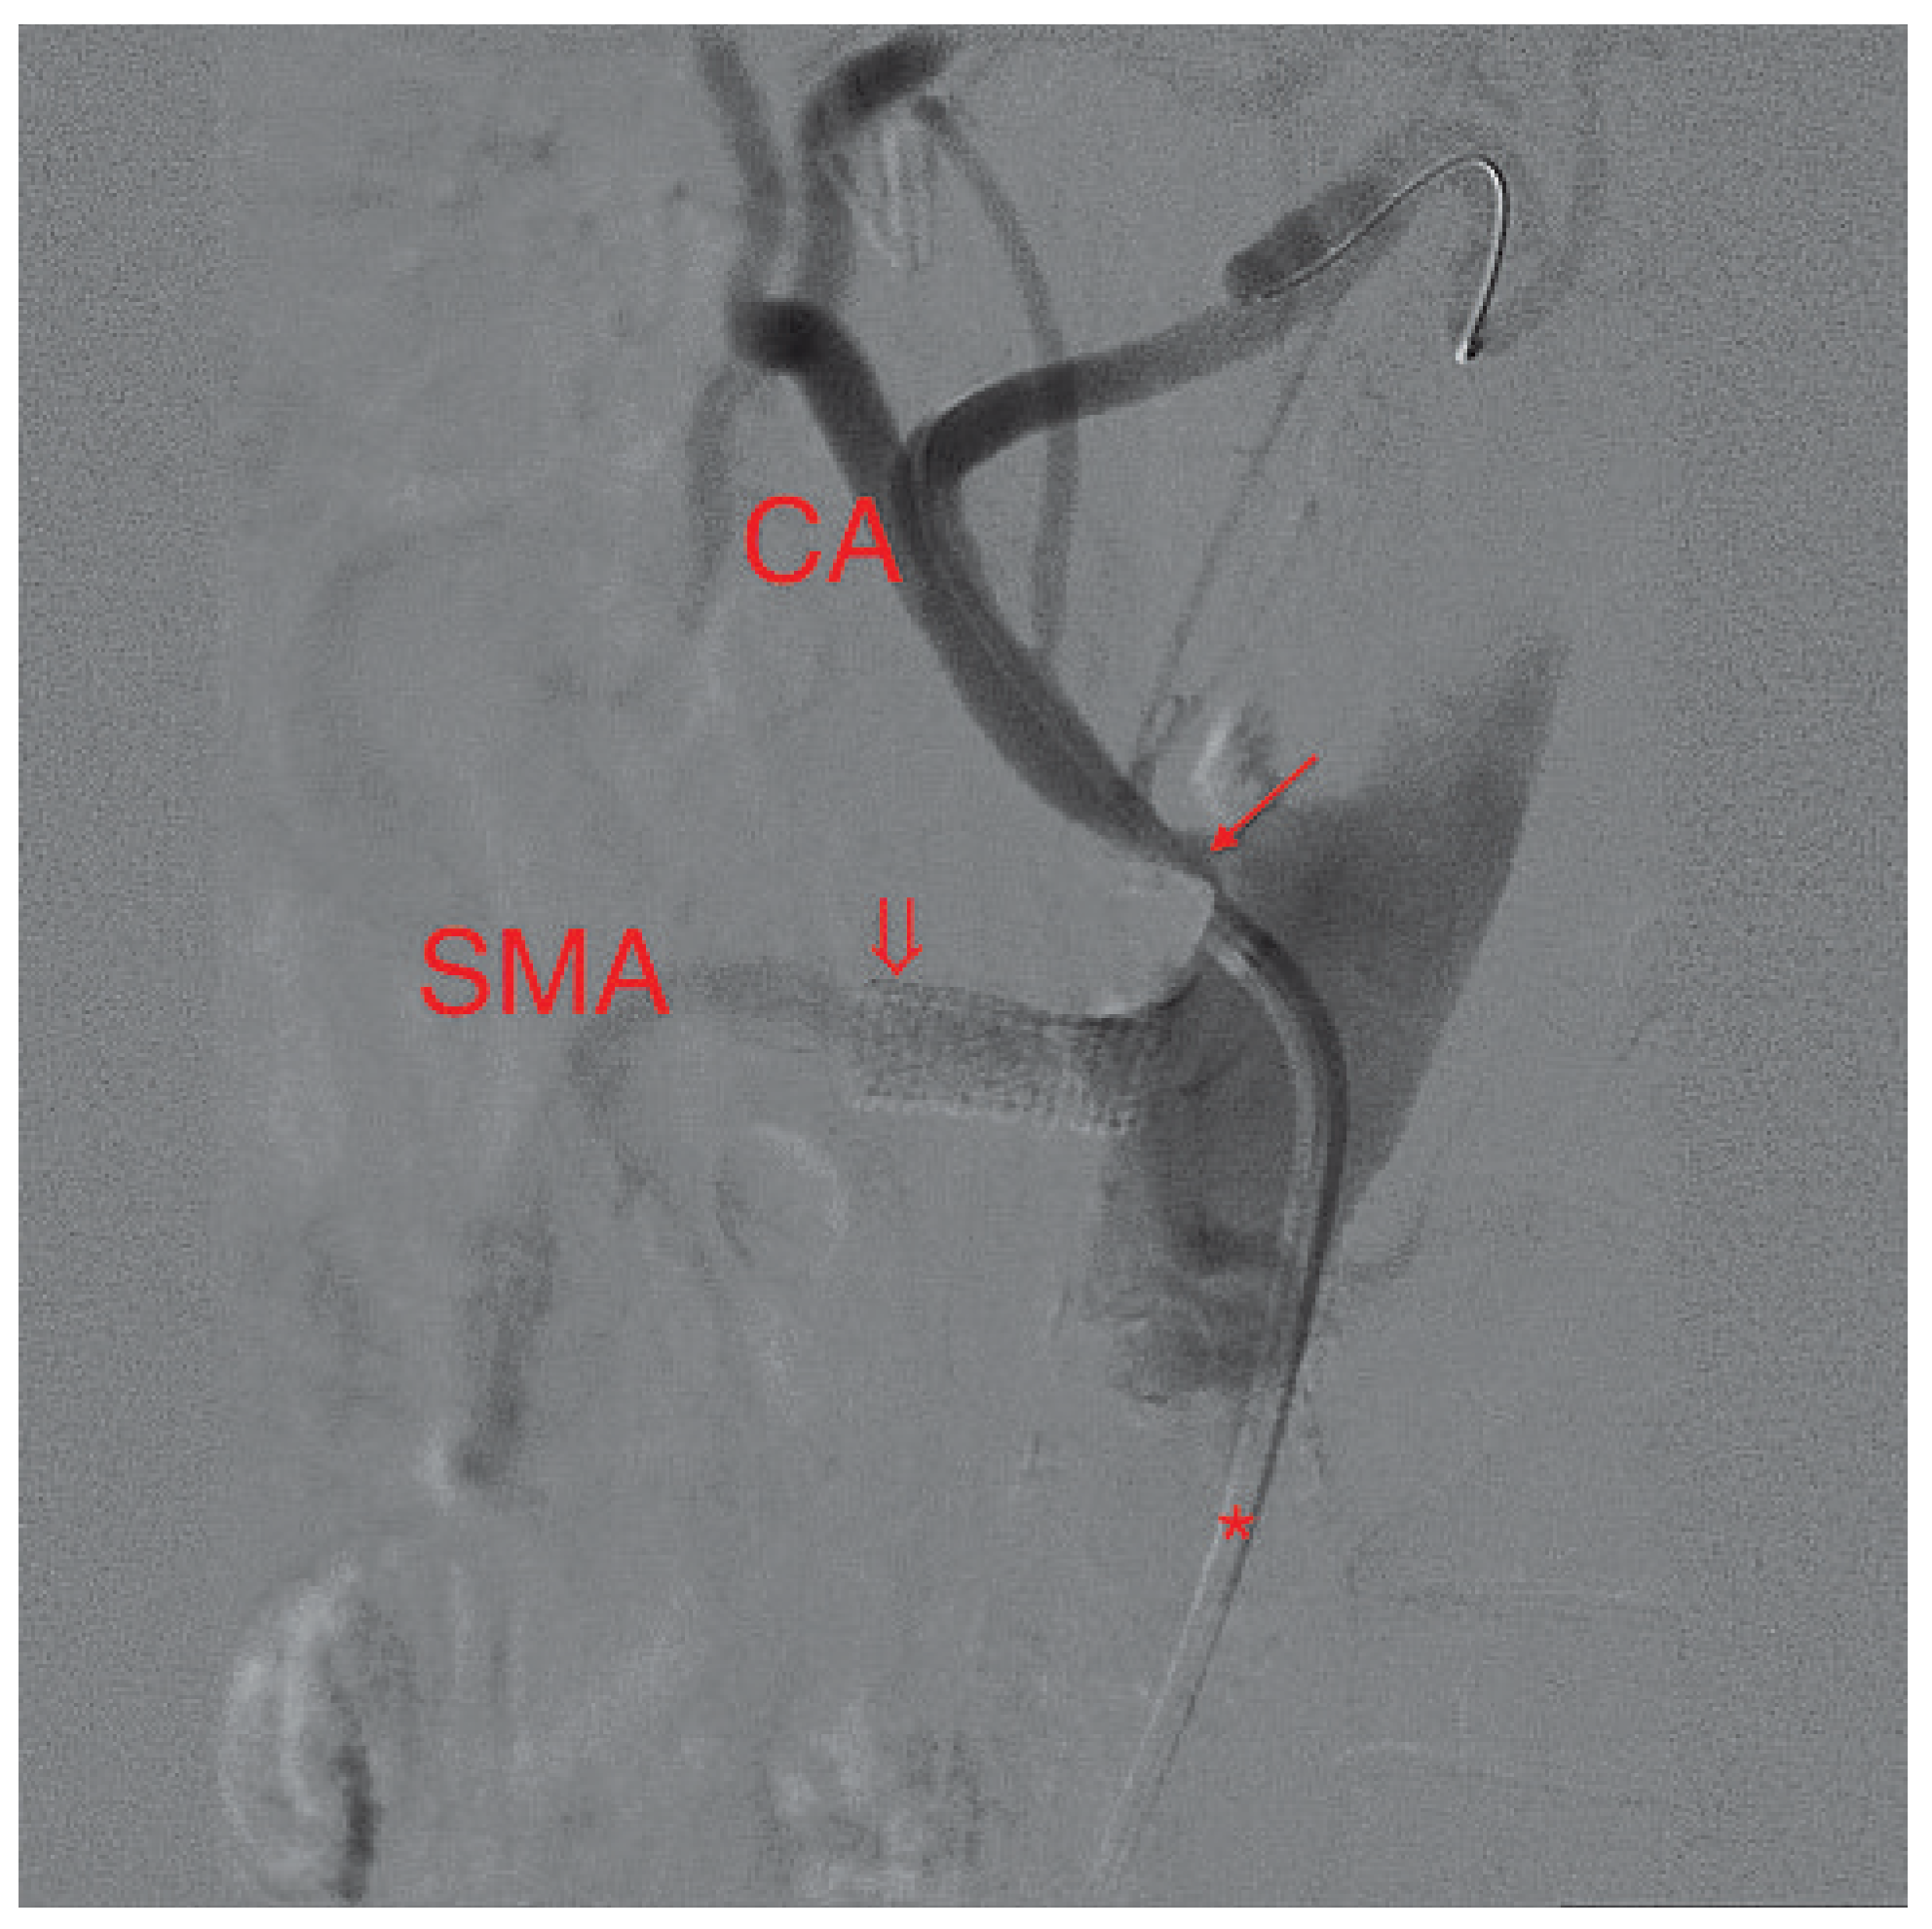

Figure 3. Digital subtraction angiography picture of the proximal celiac artery (CA) and the distal SMA, lateral projection. The catheter (*) lies at the ostium of the severely stenosed CA (arrow) – a guidewire is in place. The patent stent (arrowhead) in the SMA is clearly visible.